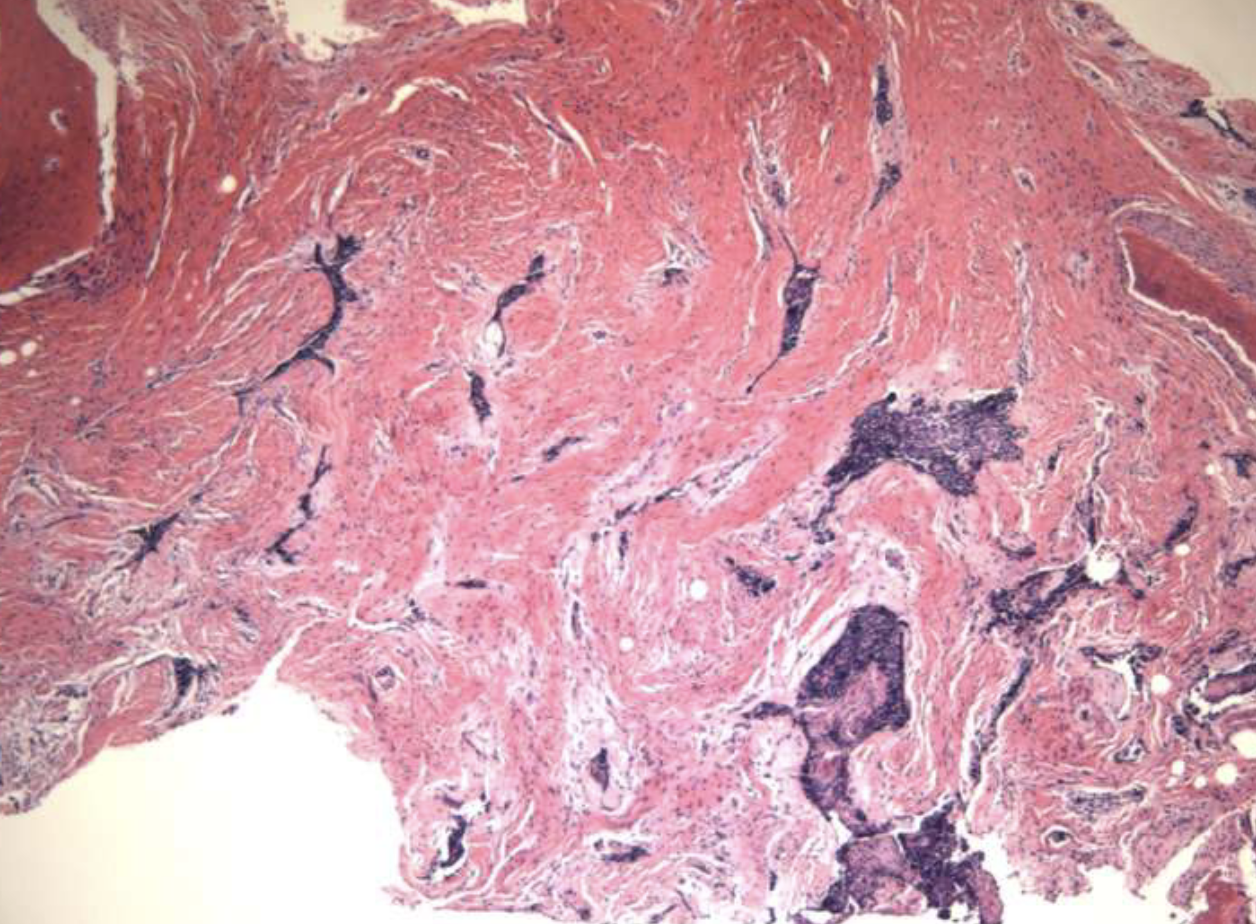

histopath features of central vascular malformations (hemangiomas)

proliferation of capillaries + endothelial cells containing abundant blood